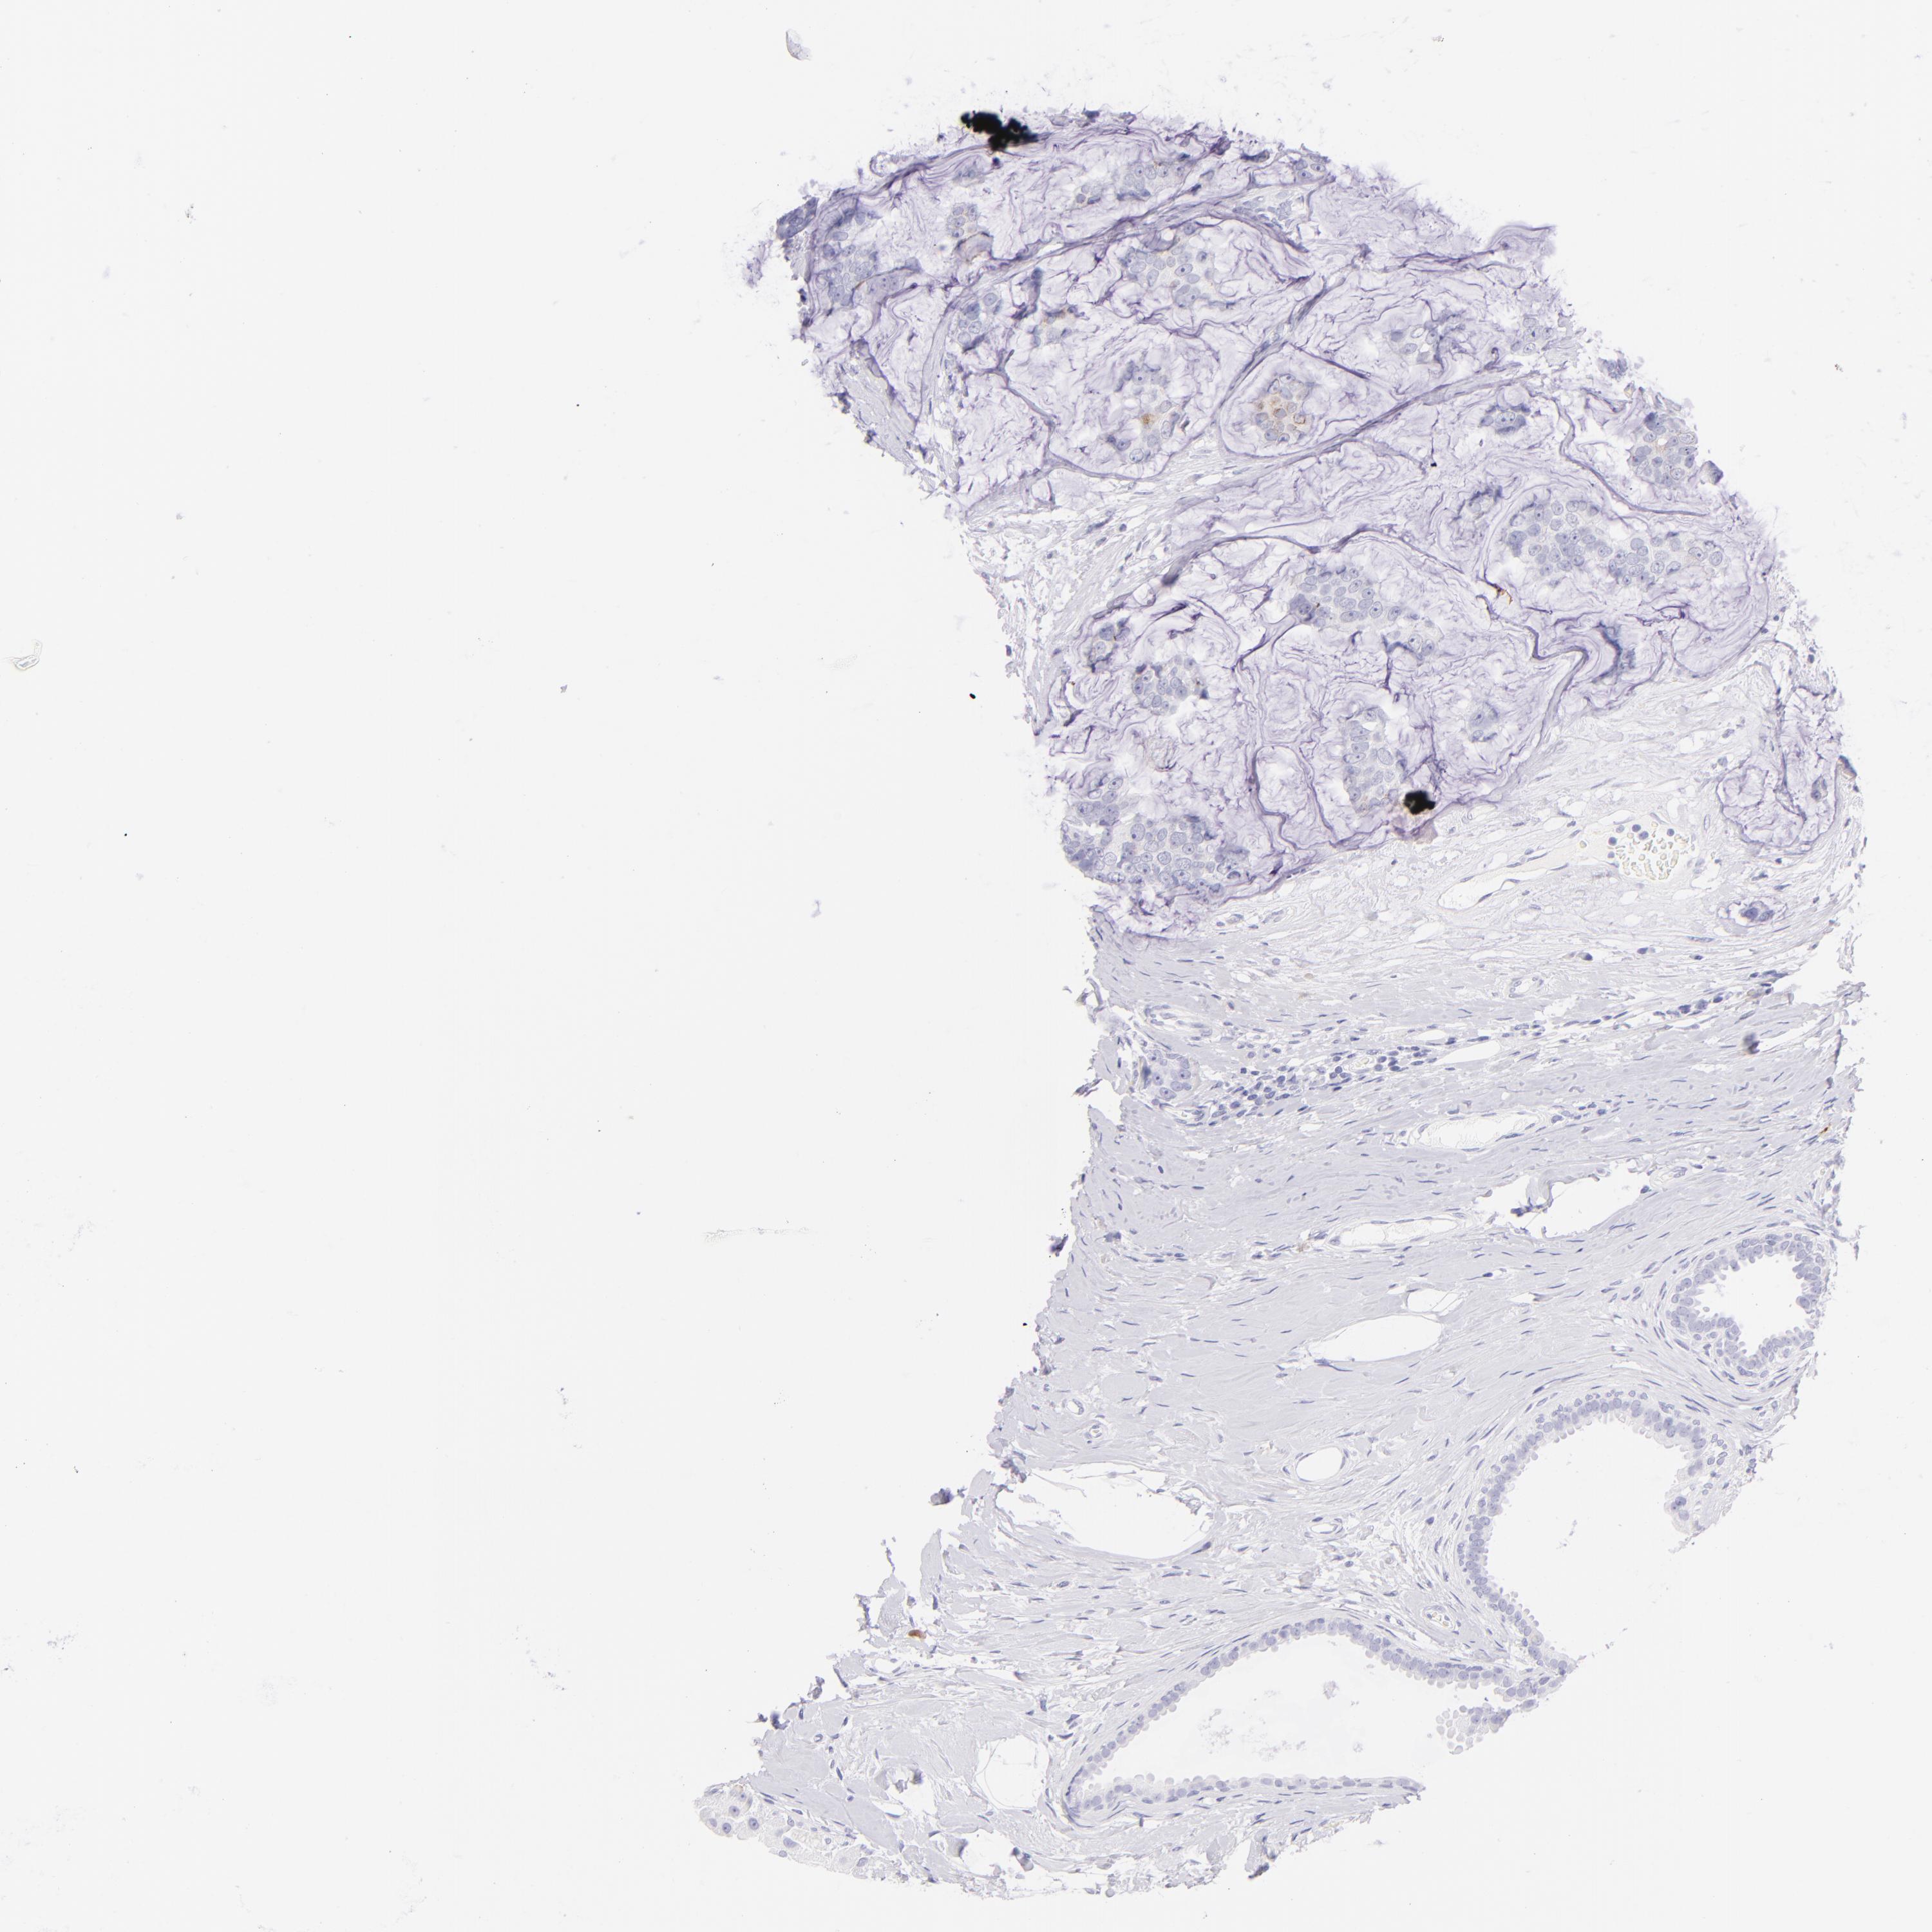

BRCA TCGA BRCA VALIDATION PROTEIN EXPRESSION

ANTIBODIES

AND

VALIDATION